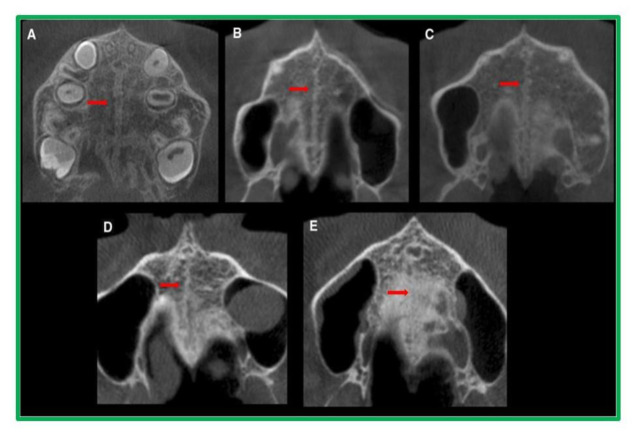

Methodology: A descriptive and prospective study was done on 110 CBCT scans of individuals aged between 10-30 years, who visited the Department of Oral Medicine and Radiology, MMCDSR, Ambala, Haryana. The visualization and classification of the stage of maturation of the mid-palatine suture was done as per Angelieri's method using a cross-sectional axial slice.

Results: Stage C was found to be the most prevalent (29.1%) with the majority of cases occurring in the 16-20 age range. Males were more likely to have Stage B, while females had Stage C. In 60 cases (54.5 percent of the overall sample), the mid-palatine suture was found to be open. The Chi-Square test results for each examiner were highly significant (p< 0.01), indicating a statistically significant association between age group and Stage distribution.